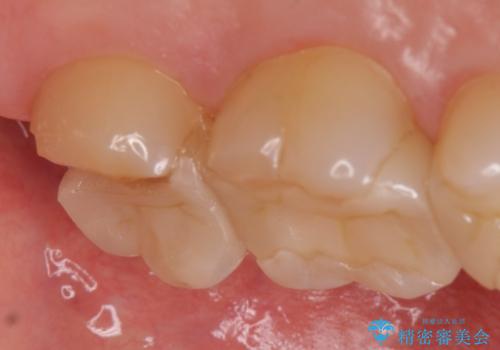

- 左上7が欠けてしまったので診て欲しいといらっしゃった方の症例です。

虫歯を除去後、オールセラミッククラウンによる補綴を行いました。